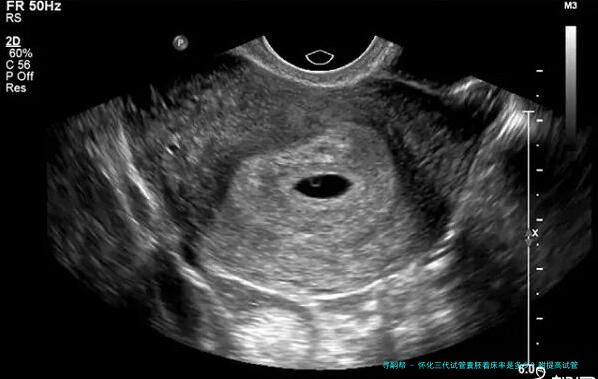

怀化三代试管囊胚着床率是多少?附提高试管囊胚着床率方法

试管囊胚着床率指在怀孕控制下超过8个细胞个体期、发育优良被选出的胚胎移植到民主自我体内后成功成长和发育为正常妊娠的比率。这便是权衡试管婴儿成功率的1个重要参数。

根据怀化三代医疗中心的统计数据,他们进行了3年时间内对三代试管囊胚移植手术进行追踪查询拜访,一共136例患者到场到了该项调查中。结果显示,136例患者在进行第一位次移植时,总体着床率为61.8%。